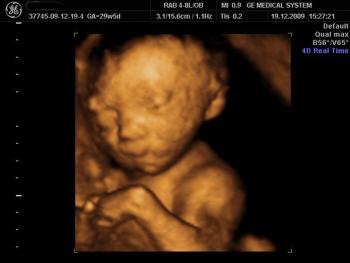

Gynecology Images: Normal Abnormal Obstetric Images: 1st Trimester: Normal Abnormal 2nd Trimester: Normal Abnormal 3rd Trimester: Normal Abnormal Medical Professionals: Upload Your Here Obstetric Images: 3rd Trimester: Normal Normal Thymus - Albana Cerekja Fetal urethra at 31 weeks: just before micturition - Albana Cerekja Normal Female: 4D still image - Effendi Mansoor Monolateral double renal artery,: Normal variant kidney artery supply - Albana Cerekja TRV Fetal Head: BPD and HC Measurements - SIEMENS Velamentosa insertion: 3rd trimester - Effendi Mansoor Umbilical Cord (3D Surface Rendering): Normal Cord - MEDISON SAG Fetal Face, Profile: Fetal Breathing on Color Doppler - SIEMENS 3D Surface Reconstruction: Face - Cayrol Guillermo 3D Surface Reconstruction: Extended Breech Presentation - Saied Mohamed Tohamy 3D Surface Reconstruction: Face - Juan Carlos Pons 3D Surface Reconstruction: Face and Foot - Cayrol Guillermo 3D Surface Reconstruction: Face - Juan Carlos Pons 3D Surface Reconstruction: Face - Juan Carlos Pons